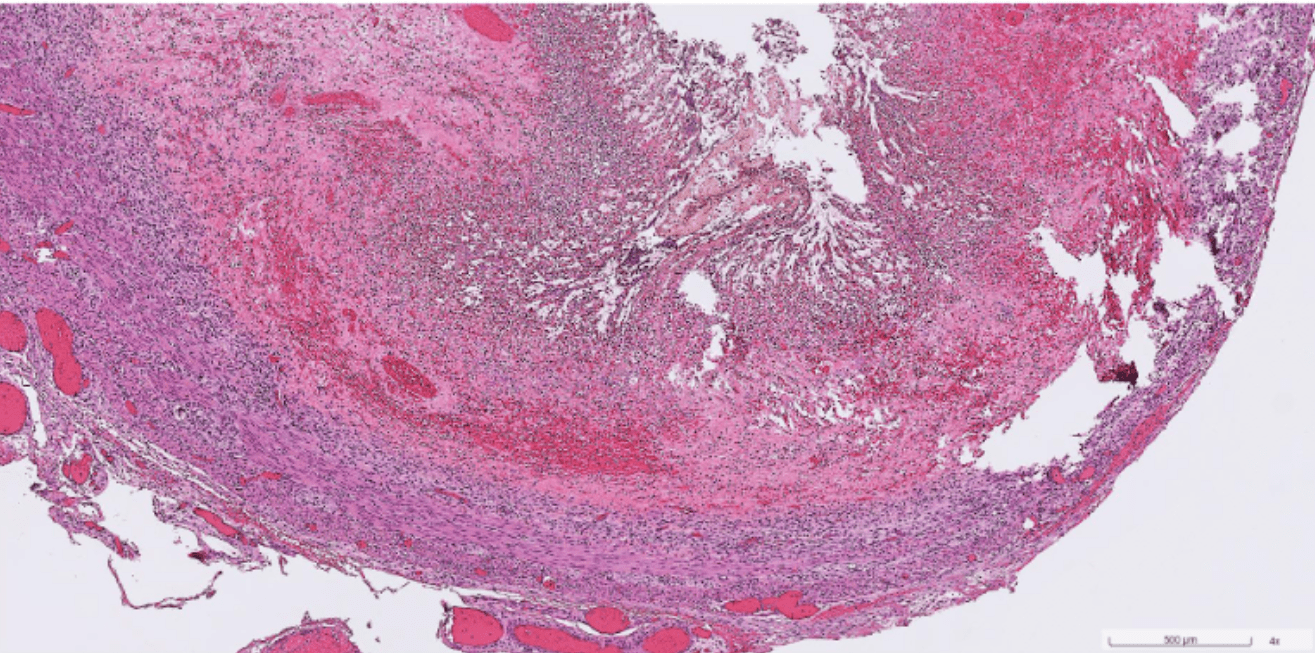

Organ: Lymph node

Diagnosis: Lymphoid hyperplasia

Descriptions:

- Increased number and size of follicles

- Follicles have distinct mantle zones and polarized germinal center

- Normal cell composition and tingible-body macrophages in the follicles